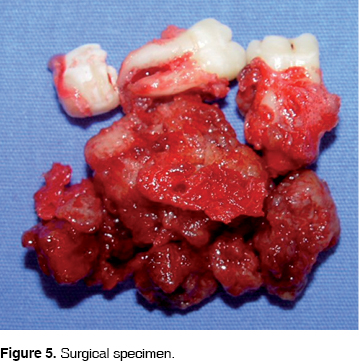

Microscopically the lesion had well defined borders, a rough surface, firm consistency and pale yellow color, producing lingual and vestibular expansion of 40 x 30 x 25 mm (Figure 5).